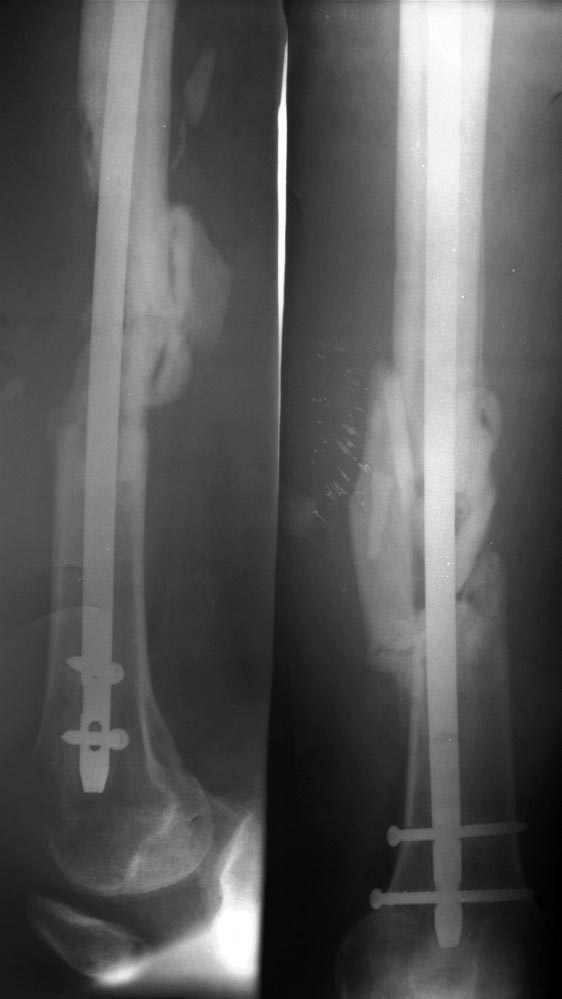

Консолидирующийся многооскольчатый перелом бедренной кости после БИОС. Какую тактику бы вы посоветовали?

ДТП, мотоциклист, сентябрь 2015, закрытый многооскольчатый перелом правой бедренной кости, переломы фаланг пальцев, локтевого отростка, лучевой кости.. Прооперирован, бедренная кость - закрытая репозиция, блокируемый интрамедулярный остеосинтез.

Дозированная нагрузка сразу, на сегодня в течении месяца нагрузка до 80%. Картина на СКТ и рентгенограмме (извините за качество, ссылки

частичная консолидация отломков, снизу вроде неплохо, проксимально слабовато. Дефект по передней поверхности бедренной кости.

Какую тактику посоветуете? Выжидательную или активную?

Я лично склоняюсь к активной - взять аутотрансплантат (продольный расщеп 2/3 малоберцевой кости, заполнить мостовидно дефект, фиксировать проксимально и дистально монокортикальными шурупами, лимитированнная боковая декортикация, укладка в зону дефекта смеси аллочипсов, аутогубки с крыла, PRF, без оголения стержня. Коллеги склоняются в выжидательной тактике. Пациент настаивает на активности, так как ему необходимо к 8 месячному сроку выйти на работу. Какие мысли? Заранее спасибо